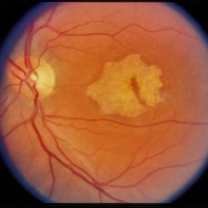

4.3 Style Transferring Neural Networks

Style transferring neural network in [16] was modified to generate new disease images. This network adopts layers from ”conv1 1” to ”conv4 1” in pre-trained VGG-19 [24] network for the encoder, whose weights are provided by ImageNet-pretrained weights. What’s more, multi-level stylization strategy proposed in [16] is applied to optimize the VGG features in different layers. Input images are three CFP images and three FA images as style images shown in Fig. 2 and 5. Six CFP images with three drusen and three GA images in Fig. 3 and Fig. 4. Also, FA images are applied to generate new images in Fig. 6 and Fig. 7. For CFP images, six images are shown in Fig. 3 and in Fig. 4. In Fig. 3, generated images contain round, discrete yellow-white dots, which are the symptom of drusen. In the same way, in Fig. 4, well-demarcated areas appear on the three images. Therefore, style transferring can generate new retinal symptom images.

Figure 2: Three CFP fundus images that are used to generate new images are seen as style images.

Figure 3: Three CFP fundus images with symptom of drusen and corresponding generated images. (a), (b), (c) Original images. (d), (e), (f) Generated images.

Figure 4: Three CFP fundus images with symptom of GA and corresponding generated images. (a), (b), (c) Original images. (d), (e), (f) Generated images.